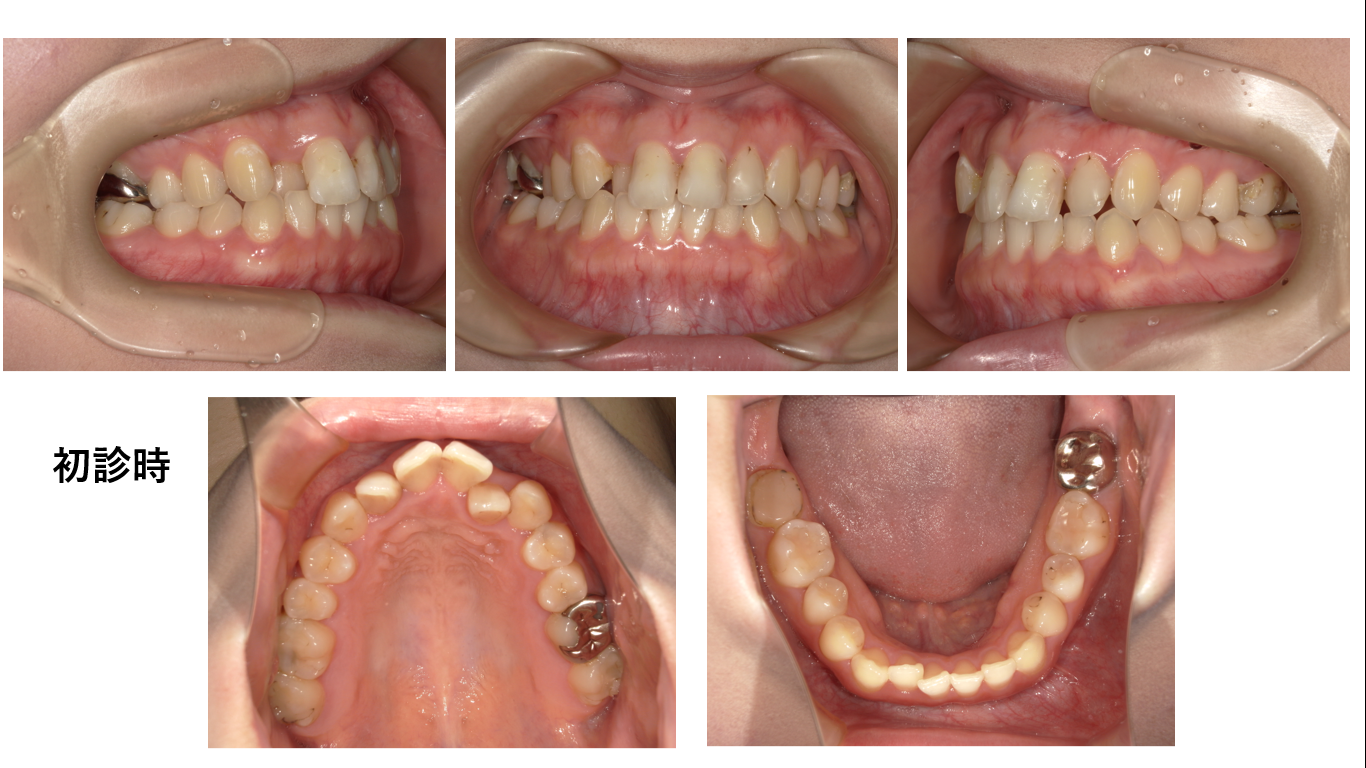

矯正症例142 AngleⅠ級、上顎前突

初診時24歳、性別:女性、治療期間2年8か月、抜歯部位:上顎左右5番、下顎左右4番,治療費総額1,030,000円(税込み)

抜歯するかしないかで悩んだ症例です。

頤が出ているtypeです。bryakiofacial typeと呼ばれるtypeです。略してブレーキィータイプとも呼ばれています。このタイプで唇が延びる人なので非抜歯で良いのではないかとおもうのですが、斜め横の顔写真をご覧ください。小さくですが、前歯場唇から出ています。

それだけで抜歯が決定です。もう一つ、笑った時の前歯の突出感が強いのです。生憎、初診時の笑った時の顔写真撮ってませんでした。残念です、お見せできません。

上の写真をご覧ください。上顎左右中切歯が、唇からはみ出ています。